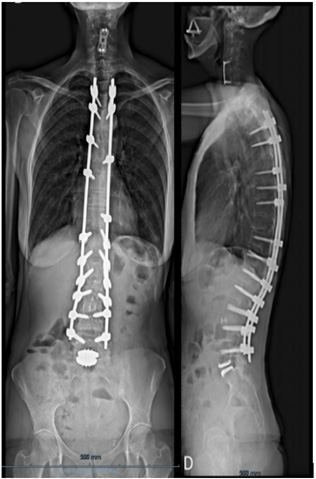

We present the case of a 40-year-old woman who presented with low back pain resistant to analgesics and rehabilitation. She was compensated and had excellent flexion and extension of her spine. The patient had a normal neurologic examination of the lower extremities. Radiographic evaluation revealed good sagittal and coronal balance, despite the co-existing mild thoracolumbar scoliosis. MRI showed Degenerative Disc Disease (DDD) at L4-L5 and L5-S1 (Figure 1A-B). She underwent a lumbar Total Disc Replacement (TDR) at L5–S1with the Charité III prosthesis and Posterior Transpedicular Dynamic Stabilization (PDS) with the Dynesys system at L4-L5 in 2001. Post-operatively, there was significant clinical improvement and the patient went back to work. In 2014, the patient complained of unremitting axial low back pain, aggravated by walking and sitting with increasing difficulty standing and looking straight ahead when walking. Concurrently, polyarthralgia and throcanteritis were also present. This motivated evaluation by Rheumatology for autoimmune disease screening which was negative. Despite being subjected to a new rehabilitation protocol, there was no clinical improvement. X rays showed a degenerative scoliosis with sagittal and coronal imbalance (Figure 2A-B) with multiple discopathies and syndesmophytes through the lumbar and thoracic spine. TDR and PDS were stable and in good position. MRI showed Dark Disc Disease at D11-D12 and from L1-L2 to L4- L5 (Figure 3A-B). The patient underwent a Transforaminal Lumbar Interbody Fusion (TLIF) at L3-L4, PDS removal and T4-L5 posterior fusion in November 2018. At the moment, the patient maintains reported significant improvement in her back pain and reduction in the requirement of analgesic medicines. Physical exam shows good spinopelvic mobility (Figure 4). Radiographs reveal good coronal and sagittal balance and satisfactory position of the total disc replacement and good fusion of the thoracic and lumbar spine proximally (Figure 5A-B) (Figure 6A-B).